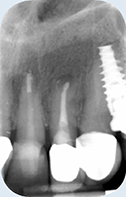

Een 72-jarige dame meldt zich op verzoek van haar tandarts voor een specifiek consult. Zij heeft in de bovenkaak twee problemen:

De brug in het eerste kwadrant heeft een probleem aan de voorste pijler: de kroon op de 15 zit los en lekt (afbeelding 1 - 3 ). De verwijzend tandarts vraagt om advies.

Solo-opname 14 en 15